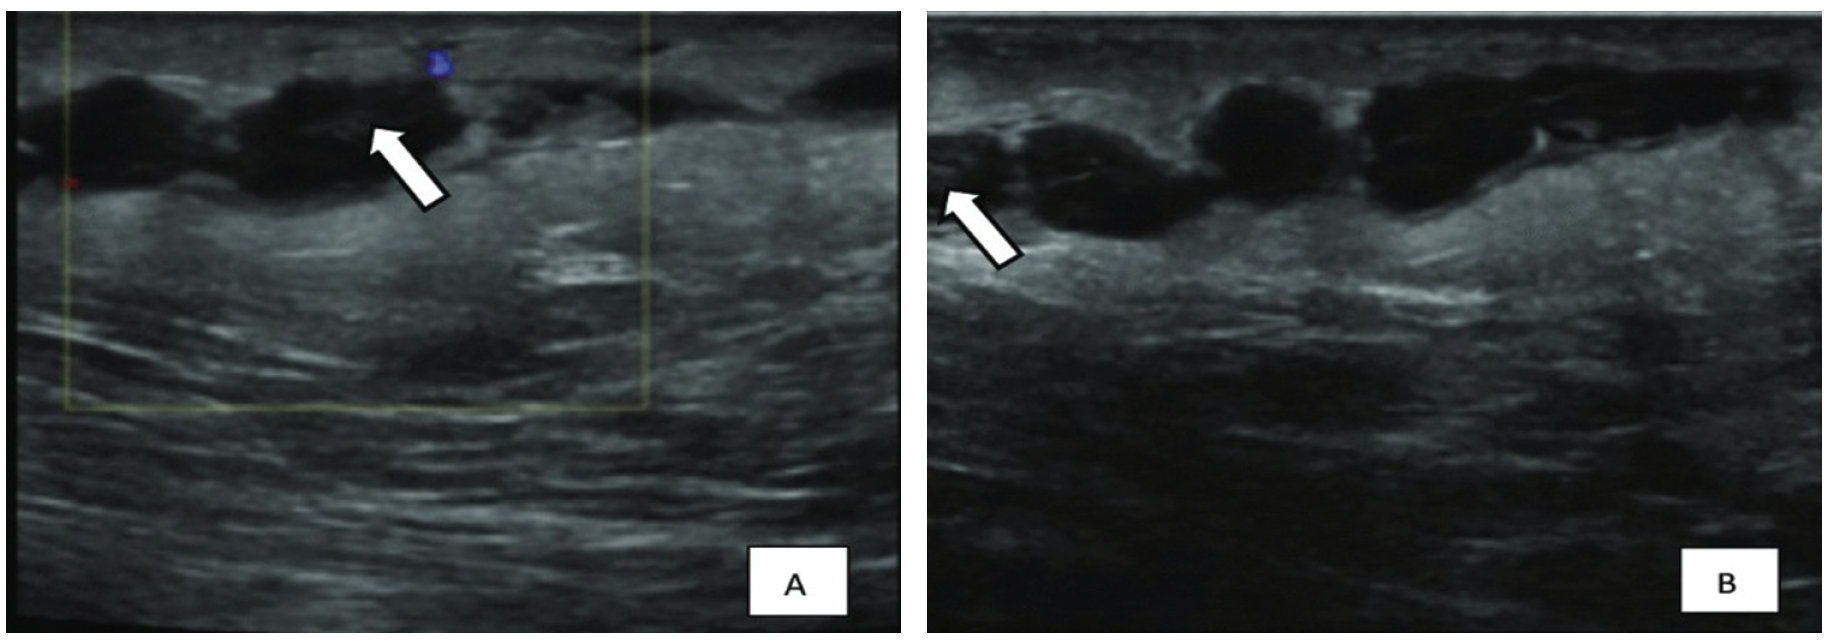

Рис. 2. Ультразвуковое исследование молочной железы при болезни Мондора

- дуплексное УЗИ с допплерографией для визуализации тромба, оценки проходимости и характера кровотока;